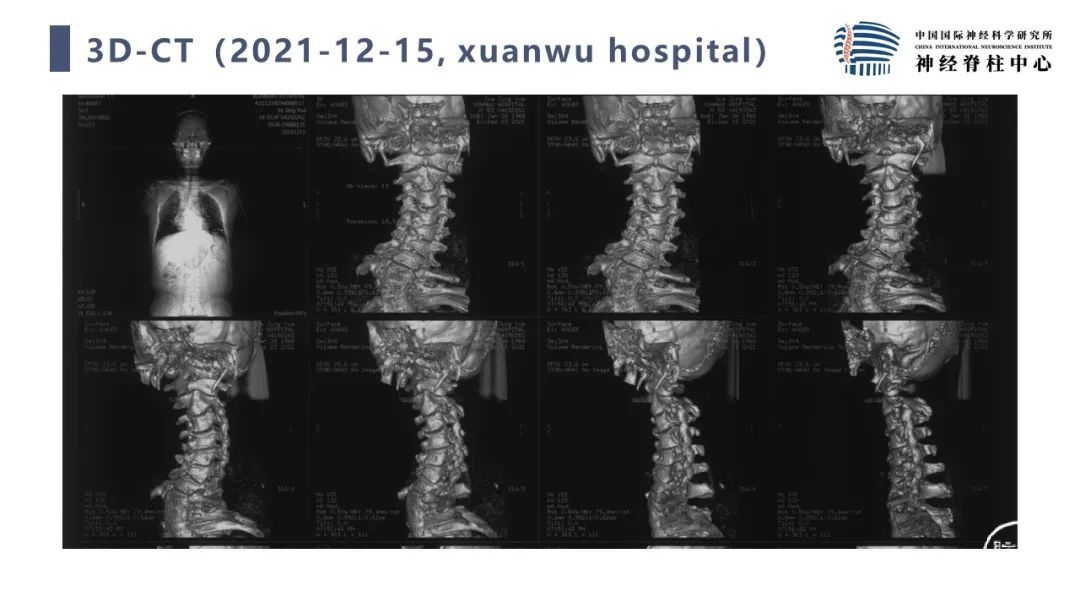

段婉茹副主任医师:脊髓栓系的治疗

首都医科大学宣武医院